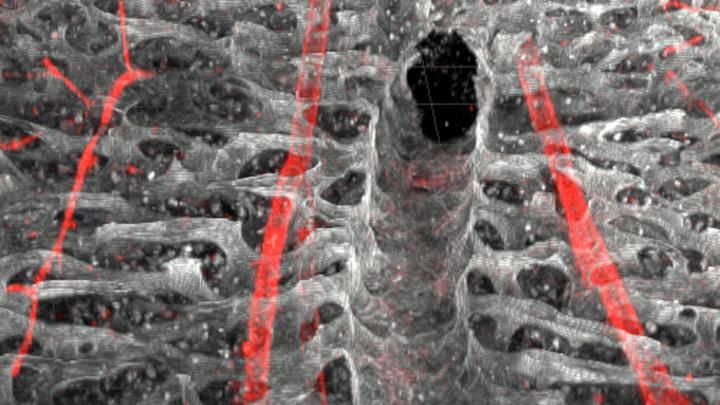

Researchers at the University of Zurich have shown for the first time that hematopoietic stem cells detect infectious agents themselves and begin to divide -- that is, without signals from growth factors. This direct production of defensive cells damages hematopoiesis in the long term, however, which could lead to malignant hematopoietic stem cell diseases at advanced age.

In studies conducted in the past few years, Manz and and his team were able to demonstrate how the cells of the vascular walls participate in the defense against infections: They produce growth factors (cytokines), thereby boosting hematopoieis. The researchers have now shown that the hematopoietic stem cells are themselves also able to detect and react to bacterial infections. "In living organisms, we were able to prove for the first time that hematopoietic stem cells have receptors that detect infections," Manz says. "As a result, latent cells are activated and start to divide and therefore produce more defense cells." This is astonishing as scientists previously assumed that hematopoietic stem cells are located in a space in the bone marrow completely protected from environmental signals, the so-called hematopoietic stem cell niche.

A receptor called TLR4 (toll-like receptor 4) is responsible for the detection of some infections. These antennae on the surface of the cell detect structures that are found only in infectious agents, such as lipopolysaccharides (LPS). If scientists administered LPS to mice, "latent" hematopoietics stem cells divided and began to produce immune cells beforehand. This detection system could have proven advantageous in evolution to provide the organism with a survival benefit, Manz assumes. As his team now shows, this process has a drawback: In the long term, damage in the hematopoietic stem cells occurs due to the reaction to infections that impair their regenerative ability and make them less fit for further hematopoieis.